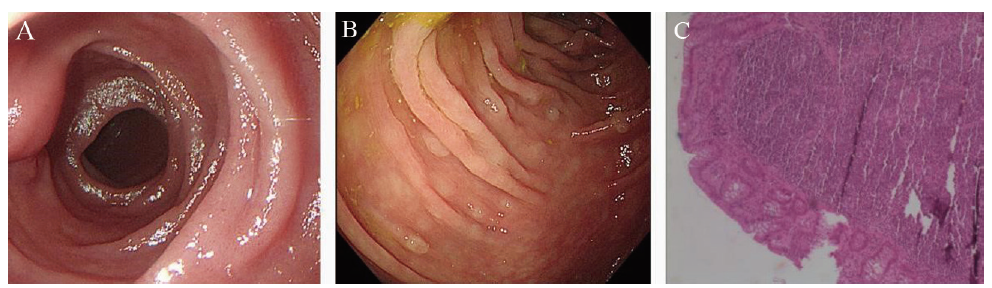

病例3 患者女,42岁,2017年12月6日因“健康体检”就诊于本院,行胃镜检查示十二指肠降部黏膜浅表性改变(图3A),当时未取活检。患者当时主诉无明显不适。2022年3月因“上腹部不适2周”于本院就诊。体格检查无殊。否认高血压、糖尿病、淋巴瘤等病史。总胆固醇>6.40 mmol/L,余实验室检查未见明显异常;胃镜示十二指肠降部见黏膜颗粒状改变(图3B),病灶处病理结果:FL(I级)(图3C);免疫组化标记结果:肿瘤细胞CD20(+),CD10(+),Bcl-2(生发中心+),Bcl-6(+),Ki-67(+,5%~15%),CD21(肿瘤性滤泡边缘+),LMO2(+),CD3(-)。结肠镜显示结肠多发息肉,病理结果示增生性息肉。右侧髂后上棘行骨髓穿刺活检,组织送检结果:流式细胞免疫表型、TCR基因重排、Ig基因重排、骨髓组织学均未见明显异常;PET/CT:全身氟代脱氧葡萄糖代谢未见异常增高;结合HE染色及免疫表型并排除系统性淋巴瘤累及十二指肠,确诊为D-FL(1级)。排除禁忌后于2022年4月起予R2方案化学治疗,具体为:“奥妥珠单抗针1 g,d1,来那度胺5 mg,d1~5”,每次奥妥珠单抗治疗后均有畏寒低热,3 d后可消退。电话随访患者至截稿日,目前化学治疗方案同前,主诉有时感上腹部不适,伴夜间盗汗,感乏力,其余无明显不适。

图3 病例3 D-FL患者胃镜及病理图片

注:A、B分别为2017年12月、2022年3月胃镜下十二指肠降部黏膜表现;C为2022年3月十二指肠降部黏膜病理(HE染色,40)。